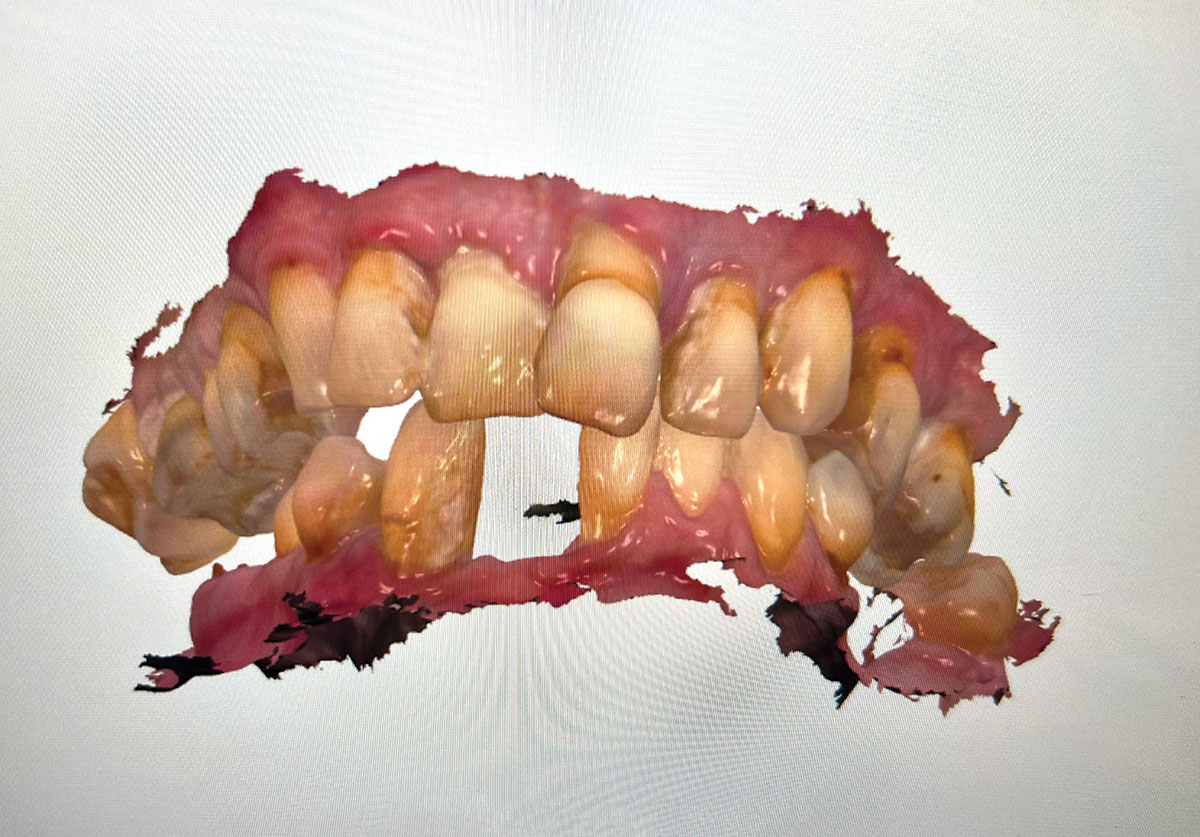

An initial appointment included a complete oral examination as well as a panoramic x-ray, CBCT scan, and intraoral surface scans of her maxilla and mandible. A comprehensive treatment plan included extraction of her mandibular teeth with immediate implant placement and insertion of a mandibular full-arch immediate fixed provisional restoration followed by a final mandibular full-arch fixed zirconia restoration.

The treatment began by addressing the patient's immediate concern, which was her mandibular situation. Her mandibular teeth were extracted, and immediate implants were placed and immediately provisionalized using a screw-retained PMMA provisional, which sat on multi-unit abutments.

After 6 months of healing (the patient delayed her final restorative treatment), the mandibular final restorative procedure was begun. A fully digital restorative protocol and workflow were followed. The first appointment for the final restoration workflow consisted of a series of intraoral scans and full-face photo-

graphy. The scans included the patient's maxillary denture, the mandibular temporary restoration that was seated in the patient's mouth, and the patient's bite.

The patient's mandibular temporary restoration was then removed from her mouth. A scan was taken of the mandibular multi-unit abutments and the surrounding soft tissue. Only the fixed soft tissue needed to be recorded, as only fixed tissue is repeatable. This type of intraoral scan is also known as the emergence profile scan.

Three implant scan bodies designed to replicate the multi-unit abutment position in the temporary were affixed to the fixed provisional restoration in the multi-unit positions with multi-unit screws. The positions were chosen to create a wide anterior-to-posterior spread. The provisional restoration with the implant scan bodies was then scanned 360 degrees.

The scan gauges were then placed onto the mandibular multi-units in the patient's mouth and retained with multi-unit screws. The choice of scan gauge height and lengths was per the fully digital restorative protocol. Two intraoral scan gauge scans were taken. The first was done in a right to left pass over the scan gauges, with care exercised to move forward in an arc so as not to go back over already-scanned segments. A second independent scan was done in a left to right arc, again with care taken not to scan any segment twice in the same scan. This completed the series of intraoral scans required to produce the restoration.